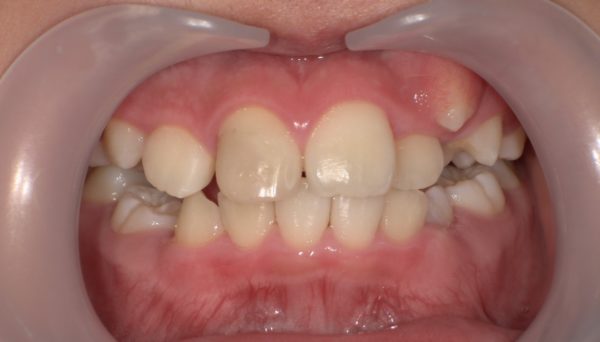

3. 軽度〜中等度の叢生(がたつき)

→ 歯並びの乱れがそれほど強くない場合。

2. 歯が非常に大きく、がたつきが強い

→ 物理的にスペースが足りないため、抜歯で調整が必要。